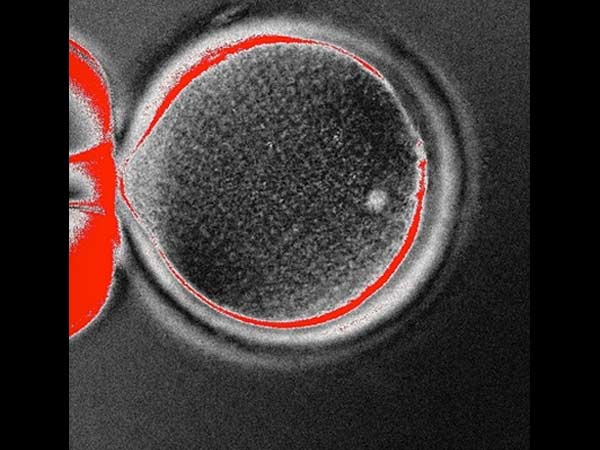

மனிதனின் தோல் செல்லுடன் பெண்ணின் சினைமுட்டையை சேர்த்து ஸ்டெம்செல் கருமுட்டையை உருவாக்கி அமெரிக்க விஞ்ஞானிகள் அபார சாதனை படைத்துள்ளனர். இதன்மூலம் சிக்கலான ஆபரேஷன்களுக்கு தேவையான ஸ்டெம்செல்களை உருவாக்க முடியும் என்று விஞ்ஞானிகள் கூறினர்.

இதுபற்றி ஆய்வுக்குழு உறுப்பினர் டாக்டர் சுக்ரத் மிடாலிபோவ் கூறும்பொழுது, 'மனிதனின் தோல் செல்லை குளோனிங் முறையில் உருவாக்கும் ஆராய்ச்சி வெற்றிகரமாக முடிந்துள்ளது. இதுபோல குளோனிங் முறையில் உருவாக்கப்படும் கருமுட்டையில் இருந்து ஸ்டெம்செல் உருவாக்கி அதன் மூலம் பல்வேறு வகையான திசு செல்களை உருவாக்க முடியும். உறுப்பு மாற்று ஆபரேஷன்களுக்கு இது முக்கிய பங்களிக்கும். உறுப்பு செல்களை வளர வைத்து, செயற்கை உறுப்புகள் தயாரிப்பது, தேவைப்படுவோருக்கு பொருத்துவதற்கான முயற்சிகளும் வெற்றி பெறும்.

குளோனிங் முறையில் தயாரிக்கப்பட்டிருக்கும் மனித ஸ்டெம்செல்லுக்கு வேறு செல்கள், திசுக்கள், உறுப்புகளை வளர வைக்கிற திறன் இருப்பது உறுதியாக தெரிகிறது. பார்வை கோளாறுகள், தண்டுவட பாதிப்புகள், பார்கின்சன்ஸ் டிசீஸ் எனப்படும் மூளை முடக்குவாதம், நரம்பு மண்டல பாதிப்புகள் ஆகியவற்றால் பாதிக்கப்பட்டவர்களின் செல்லை எடுத்து அதை கருமுட்டையாக மாற்றி வளர வைத்தால் செல்களின் ஜெராக்ஸ் பிரதிகளை உருவாக்க முடியும்.